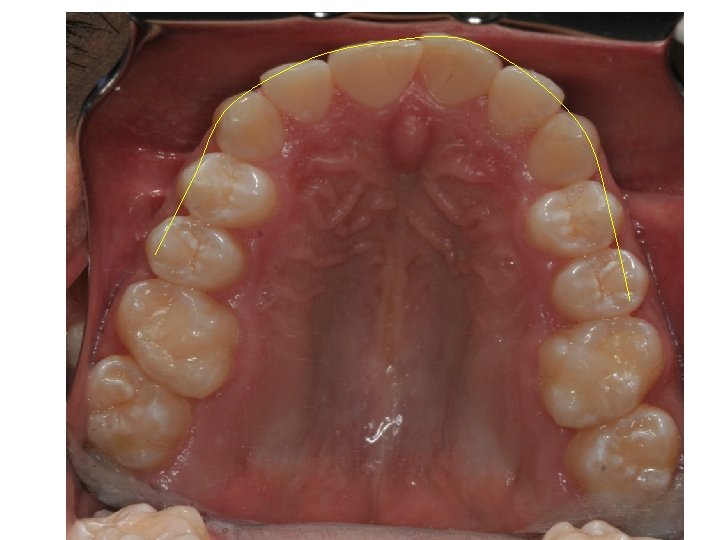

SPACE MEASUREMENT OF CROWDED UPPER SECTION 7. 36 7. 81 8. 18 6. 84

ARCH PERIMETER MEAUSURMENT